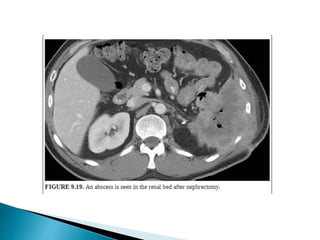

4. Abscess

1. Hematoma 2. Urinomas 3.Lymphocele 4. Abscess